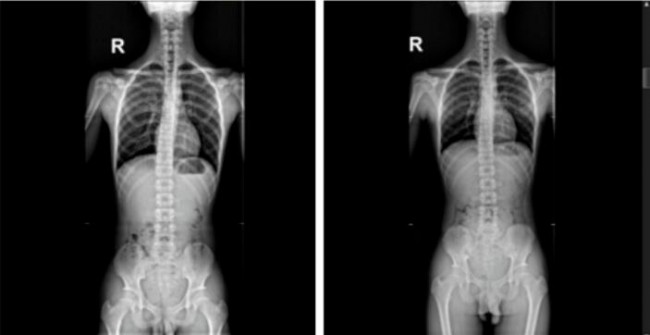

案例二:患者姜某,男性,15岁,鞋垫穿戴时间1年,有效改善后跟外翻及脊柱侧凸。